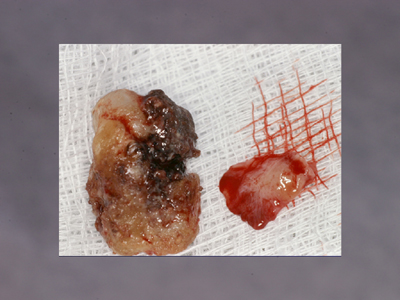

浮腫性の歯肉、全顎にわたりpd8〜10mm、著しい動揺がみられる重症例です。

(下顎前歯部歯肉に注目ください)

初診から7wブラッシング指導のみ。歯肉に変化はみられますが、あえてまだスケーリングはせずもう少し歯肉が変化するのを待ちます。

さらにその3w後。浮腫性の歯肉が乾いた感じに変化しました。歯肉が治ろうとするサインです!この時を見逃さず、ポケット底から縁上まで1歯につき1回でルートプレーニングをします。

1ヶ月後、プロービングデプスは2〜3mmに改善しました。